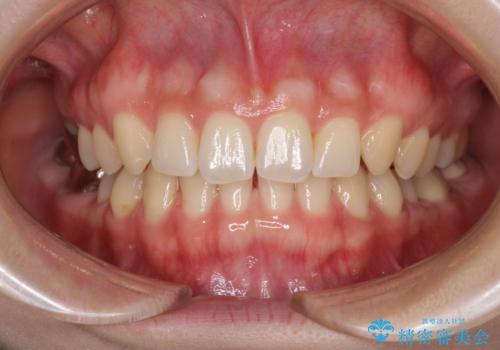

隙間だらけの歯列をきれいに インビザライン矯正とセラミック補綴治療

- 前歯の隙間と奥歯の目立つ銀歯を気にして来院された患者様です。

インビザラインにより下顎前歯の隙間を閉じるとともに、奥歯の咬み合わせを改善させることとしました。

矯正治療後には、銀歯のクラウンをセラミッククラウンへ替える補綴治療を行うこととしました。